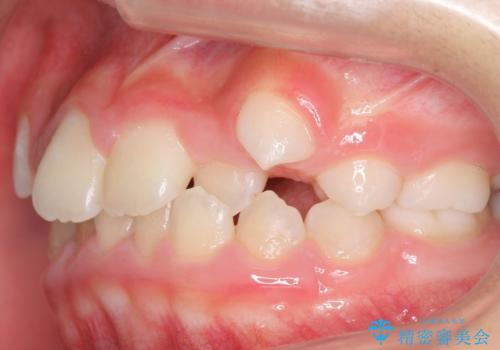

八重歯 歯を抜かずにインビザラインで

- 八重歯を主訴に来院。

抜かずに歯を少し削って入れる方法で並べました。

10代のうちに矯正をしておくと歯の移動は簡単で、歯ぐきも下がりにくいです。